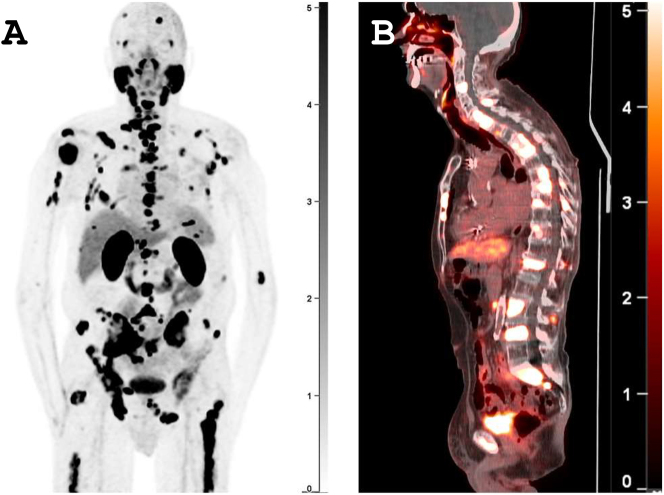

随着前列腺特异性膜抗原(PSMA)靶向正电子发射断层扫描(PET)成像技术的出现,前列腺癌(PCa)的诊断和预后发生了重大转变。与传统成像方法相比,PSMA-PET成像在检测前列腺癌、其生化复发和转移部位方面具有更高的灵敏度和特异性。这种转变现在与人工智能(AI)的快速发展——包括生成式人工智能的出现——相交叉。然而,与PSMA-PET成像相关的独特临床挑战仍然需要解决,以确保其继续广泛整合到临床护理和研究试验中。其中一些挑战是病变摄取的动态范围非常广,可能与疾病部位相邻的器官的良性摄取,训练人工智能模型的大数据集不足,以及图像中的人工制品。生成人工智能模型,如生成对抗网络、变分自编码器、扩散模型和大型语言模型,在克服各种成像模式(包括PET、计算机断层扫描、磁共振成像、超声等)的许多此类挑战方面发挥了至关重要的作用。在这篇综述文章中,我们深入探讨了生成式人工智能在增强PSMA-PET成像和图像分析的鲁棒性和广泛应用方面的潜在作用,从现有文献中吸取了见解,同时也探讨了该领域当前的局限性和未来的方向。

The diagnosis and prognosis of Prostate cancer (PCa) have undergone a significant transformation with the advent of prostate-specific membrane antigen (PSMA)-targeted positron emission tomography (PET) imaging. PSMA-PET imaging has demonstrated superior performance compared to conventional imaging methods by detecting PCa, its biochemical recurrence, and sites of metastasis with higher sensitivity and specificity. That transformation now intersects with rapid advances in artificial intelligence (AI) - including the emergence of generative AI. However, there are unique clinical challenges associated with PSMA-PET imaging that still need to be addressed to ensure its continued widespread integration into clinical care and research trials. Some of those challenges are the very wide dynamic range of lesion uptake, benign uptake in organs that may be adjacent to sites of disease, insufficient large datasets for training AI models, as well as artifacts in the images. Generative AI models, e.g., generative adversarial networks, variational autoencoders, diffusion models, and large language models have played crucial roles in overcoming many such challenges across various imaging modalities, including PET, computed tomography, magnetic resonance imaging, ultrasound, etc. In this review article, we delve into the potential role of generative AI in enhancing the robustness and widespread utilization of PSMA-PET imaging and image analysis, drawing insights from existing literature while also exploring current limitations and future directions in this domain.